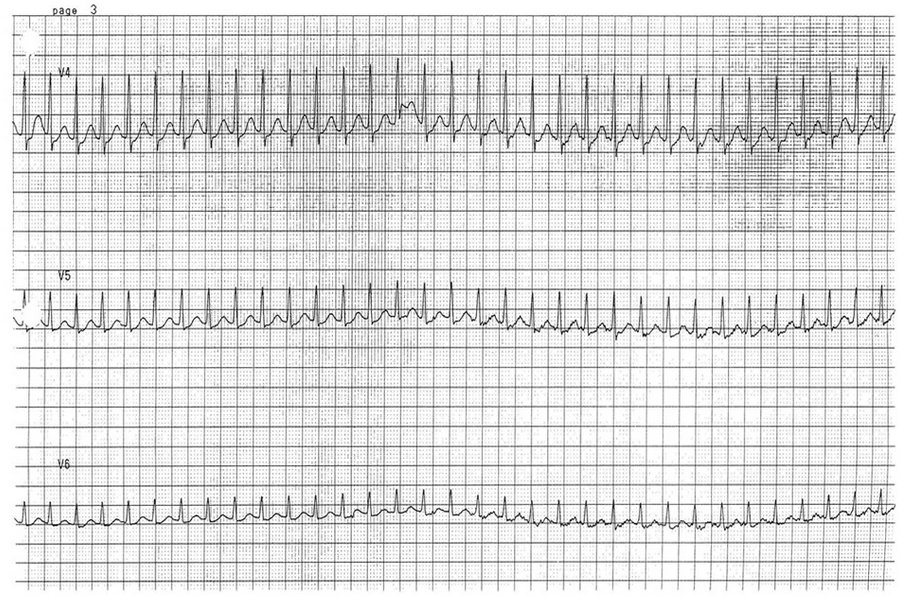

Furthermore, the widths of the QRS are also irregular and vary between beats (best seen in the six-lead rhythm strip or lead V4 of the 12-lead ECG).

These three criteria, namely wide complex tachyarrhythmia, irregularly irregular rhythm, and varying widths of the QRS complexes, should prompt consideration of preexcited atrial fibrillation or atrial fibrillation in a patient with an accessory conduction pathway. This is also called preexcitation syndrome or Wolff-Parkinson-White syndrome. Patients with preexcitation syndrome have an accessory conduction pathway that directly connects the atria with the ventricles and bypasses the atrioventricular (AV) node. If conduction occurs through this accessory pathway, the ventricles are activated sooner than when the impulse travels through the AV node. This activation, which is referred to as preexcitation, results in the classic ECG findings of shortened PR interval and widened QRS complex due to a delta wave (red arrows in Figure 3).

A 28-year-old man with stage IIC testicular seminoma is being treated with bleomycin, etoposide, and cisplatin chemotherapy. During his third cycle, a rapid response is called to his room for tachycardia. Vital signs include a temperature of 37°C, heart rate of 180/min, BP of 111/72 mm Hg, and respiratory rate of 22/min. A 12-lead ECG (Figure 1) and six-lead rhythm strip (Figure 2) are obtained.